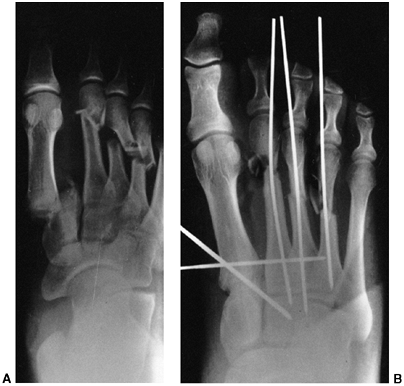

nerve function. Neurovascular problems are frequent, and fracture